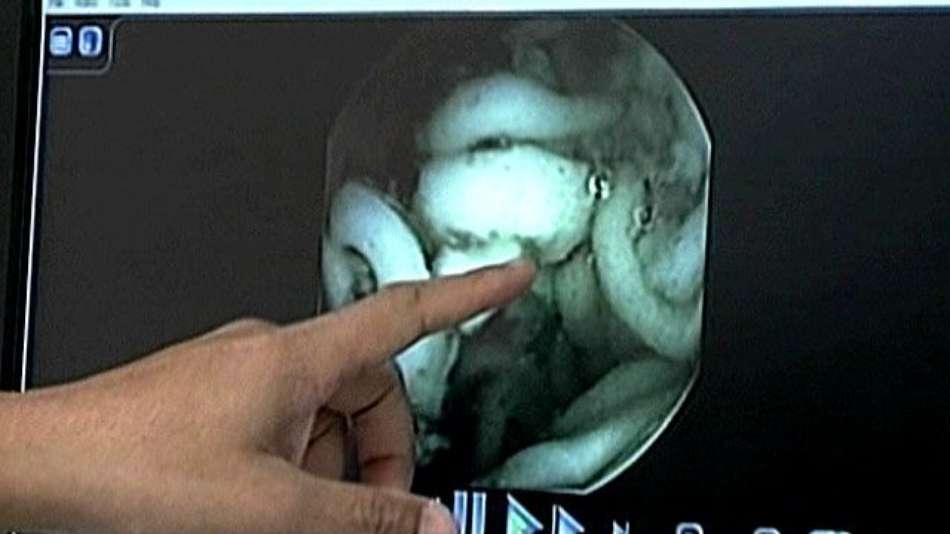

Vídeo mostra como é lenta a digestão de macarrão instantâneo

Microcâmera registra a diferença na duração da digestão de macarrão instantâneo industrializado e caseiro